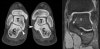

CT : 선천성 족근골융합증, 족근 결합(Congenital tarsal coalition, Synostosis)

Bony coaliation 증례는 적고, 대부분은 다른 선천 기형의 부분 증상입니다(뼈의 변형이 있어 X-ray나 CT로 진단 가능합니다).

통증을 일으켜 문제가 되는 것은 Cartiligenous coaliation이며, 이것은 결코 적지 않습니다. 다만 X-ray에서는 융합되어 있는 것으로는 보이지 않으며 관절종간이 좁거나 불규칙적입니다(뼈가 연속되지 않아도 관절공간이 좁거나 불규칙적한 형상으로부터 섬유성 융합을 진단할 수 있다).